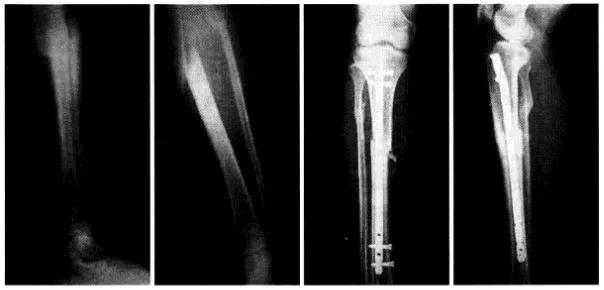

胫腓骨骨折应用交锁髓内针治疗骨折愈合